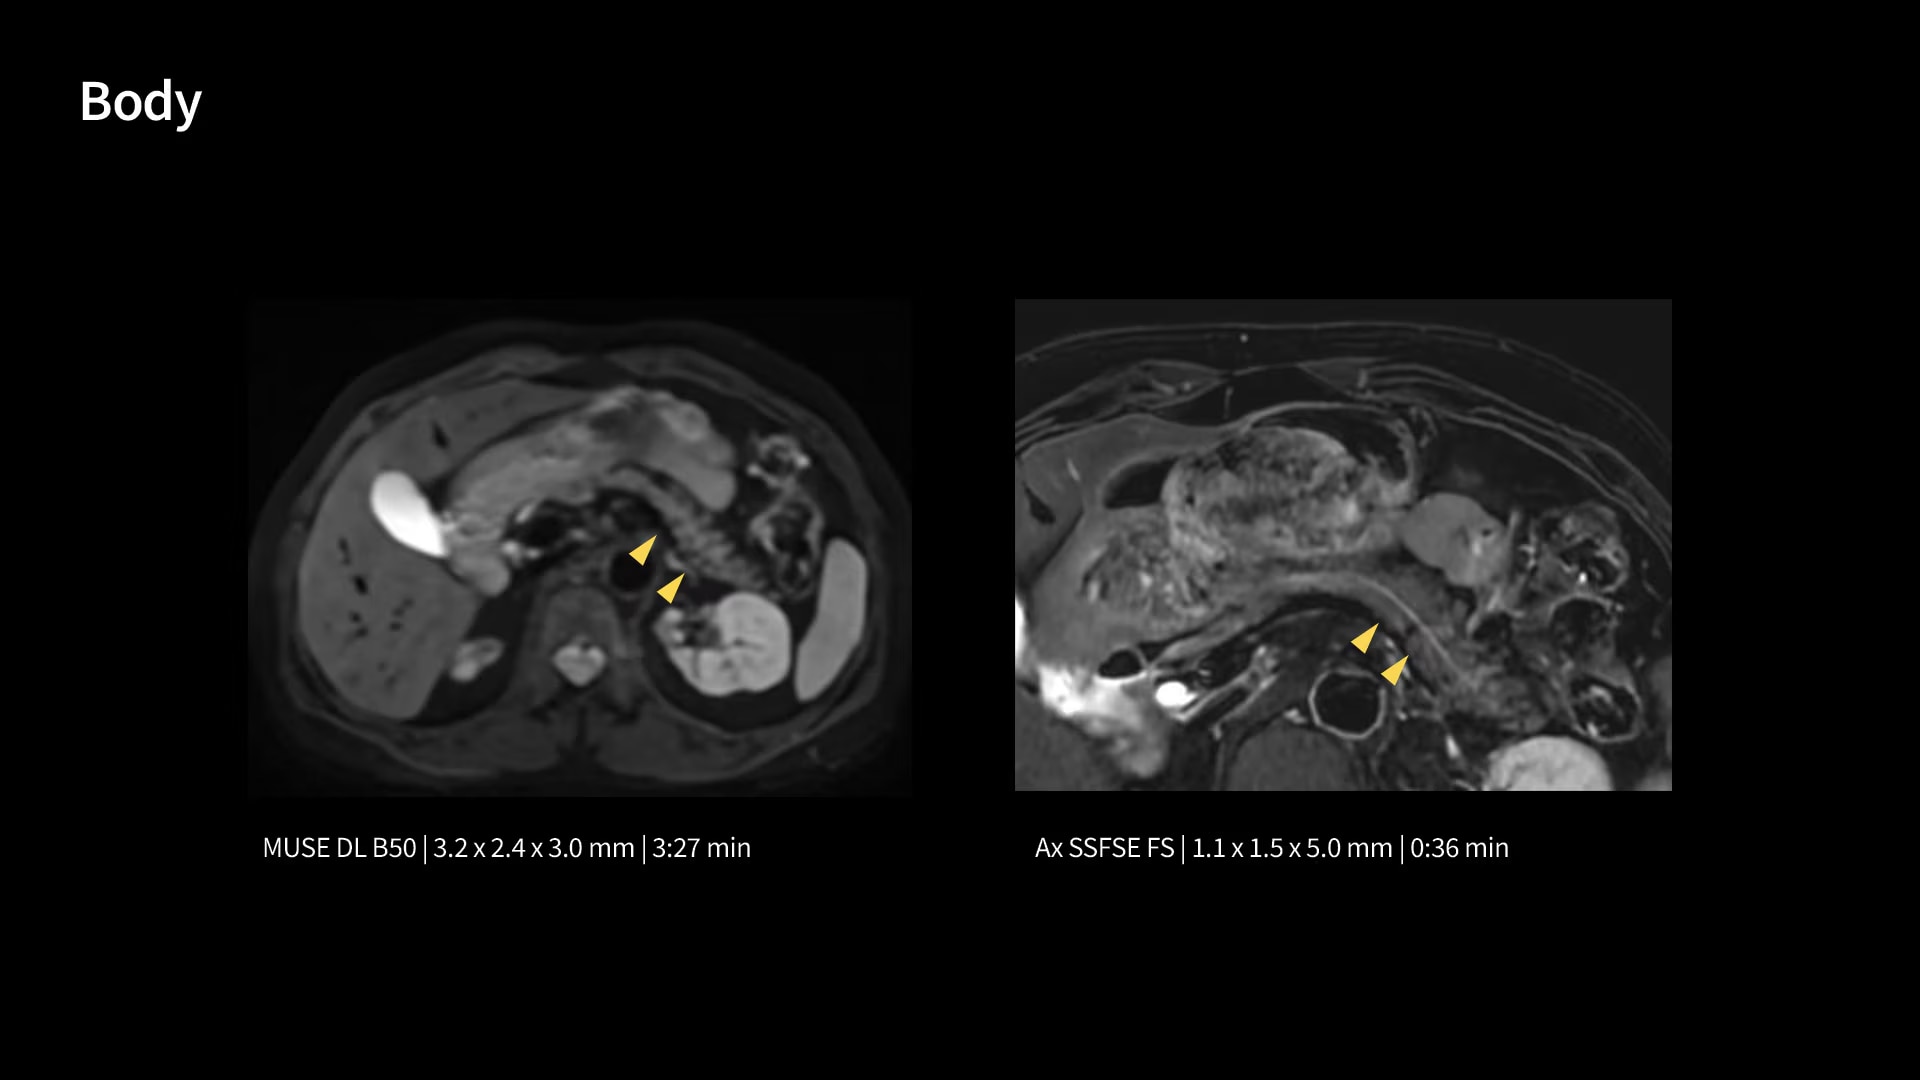

In oncological assessments, diffusion imaging is a critical clinical indicator. SIGNA Sprint offers clearer diffusion, reduced distortion, and improved SNR.¹

Within cardiovascular diseases, the functional assessment of the heart is an essential imaging application. SIGNA Sprint is powered by built-in AI technologies—Sonic DL™, AIR Recon DL and AIR x™—enabling high-quality imaging even in the most demanding anatomies.